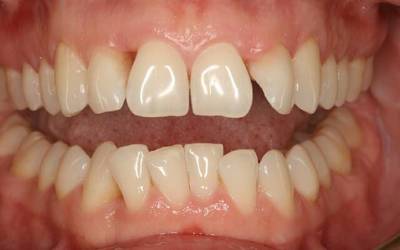

Локальный острый

Острый пародонтит встречается достаточно редко. Начинается заболевание резко, практически без начальных симптомов. Характеризуется острой болью при чистке зубов и жевании. Дёсны воспаляются, появляется кровоточивость. Чаще всего пародонтит этой стадии локализован, то есть распространяется на несколько зубов, а не на весь ряд.

К возникновению заболевания приводят патогенные микробы, механические и химические воздействия, а также неправильная установка пломбы или травма десны.

Фото 1. Острый локальный пародонтит. Воспалены десны в области двух зубов, наблюдается покраснение и кровотечение.

Диагностика острого пародонтита происходит быстро. Выявить заболевание можно уже на этапе простого осмотра специалистом. Чаще всего, острый пародонтит успешно вылечивается. Риск рецидива практически равен нулю.